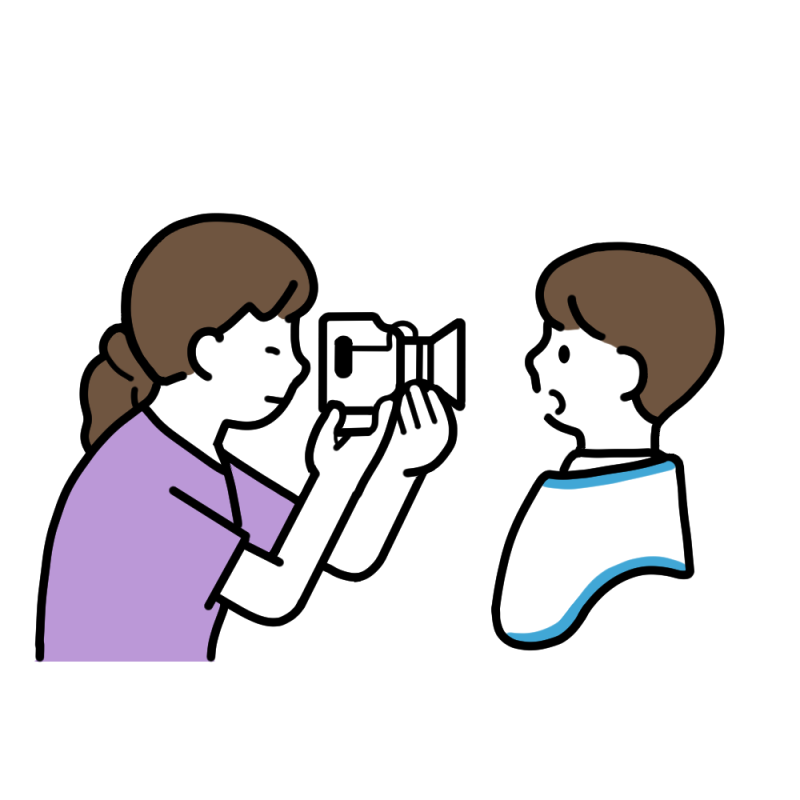

精密検査

カウンセリング後、矯正治療を始める前に必ず行うのが精密検査です。現在のお口の状態を把握し、今後の治療方針を決めるうえで非常に重要となります。

精密検査は主に4つの項目にわかれており、それぞれが適切な矯正治療を行うための診断に非常に重要な項目となります。詳しくは下記ブログをご覧ください。